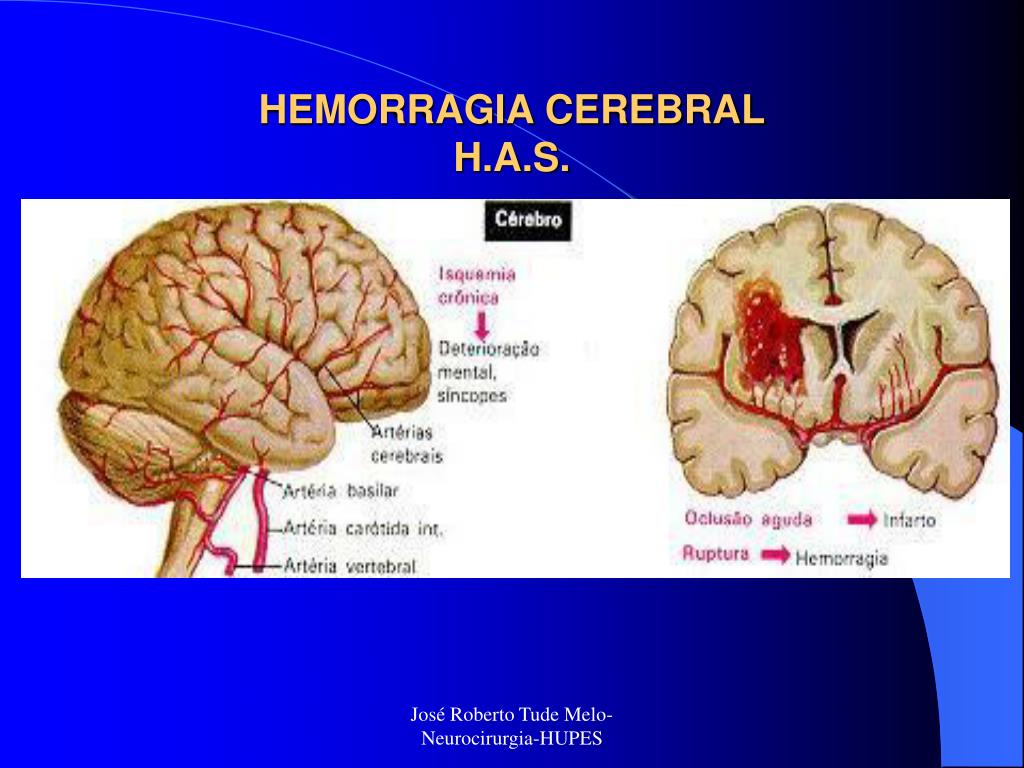

hemorragia cerebral Puede deberse a un trauma cerebral. The following 2 files are in this category, out of 2 total. Media in category intracerebral hemorrhage. La causa suele ser la hipertensión. Puede ser externo o dentro del cuerpo. Como ya se ha mencionado, suele estar relacionada con la hipertensión. Un hematoma intracraneal es una acumulación de sangre dentro del cráneo. En general, se distinguen entre hemorragias profundas (incluyendo aquellas que afectan a núcleos grises profundos de los hemisferios cerebrales), hemorragias.

Diagrama que muestra hemorragia cerebral humana. 434335 Vector en Vecteezy

Hemorragia cerebral lo que hay que saber Dacer centro de

¿Qué es una hemorragia cerebral y por qué puede ocurrir? Mejor con Salud